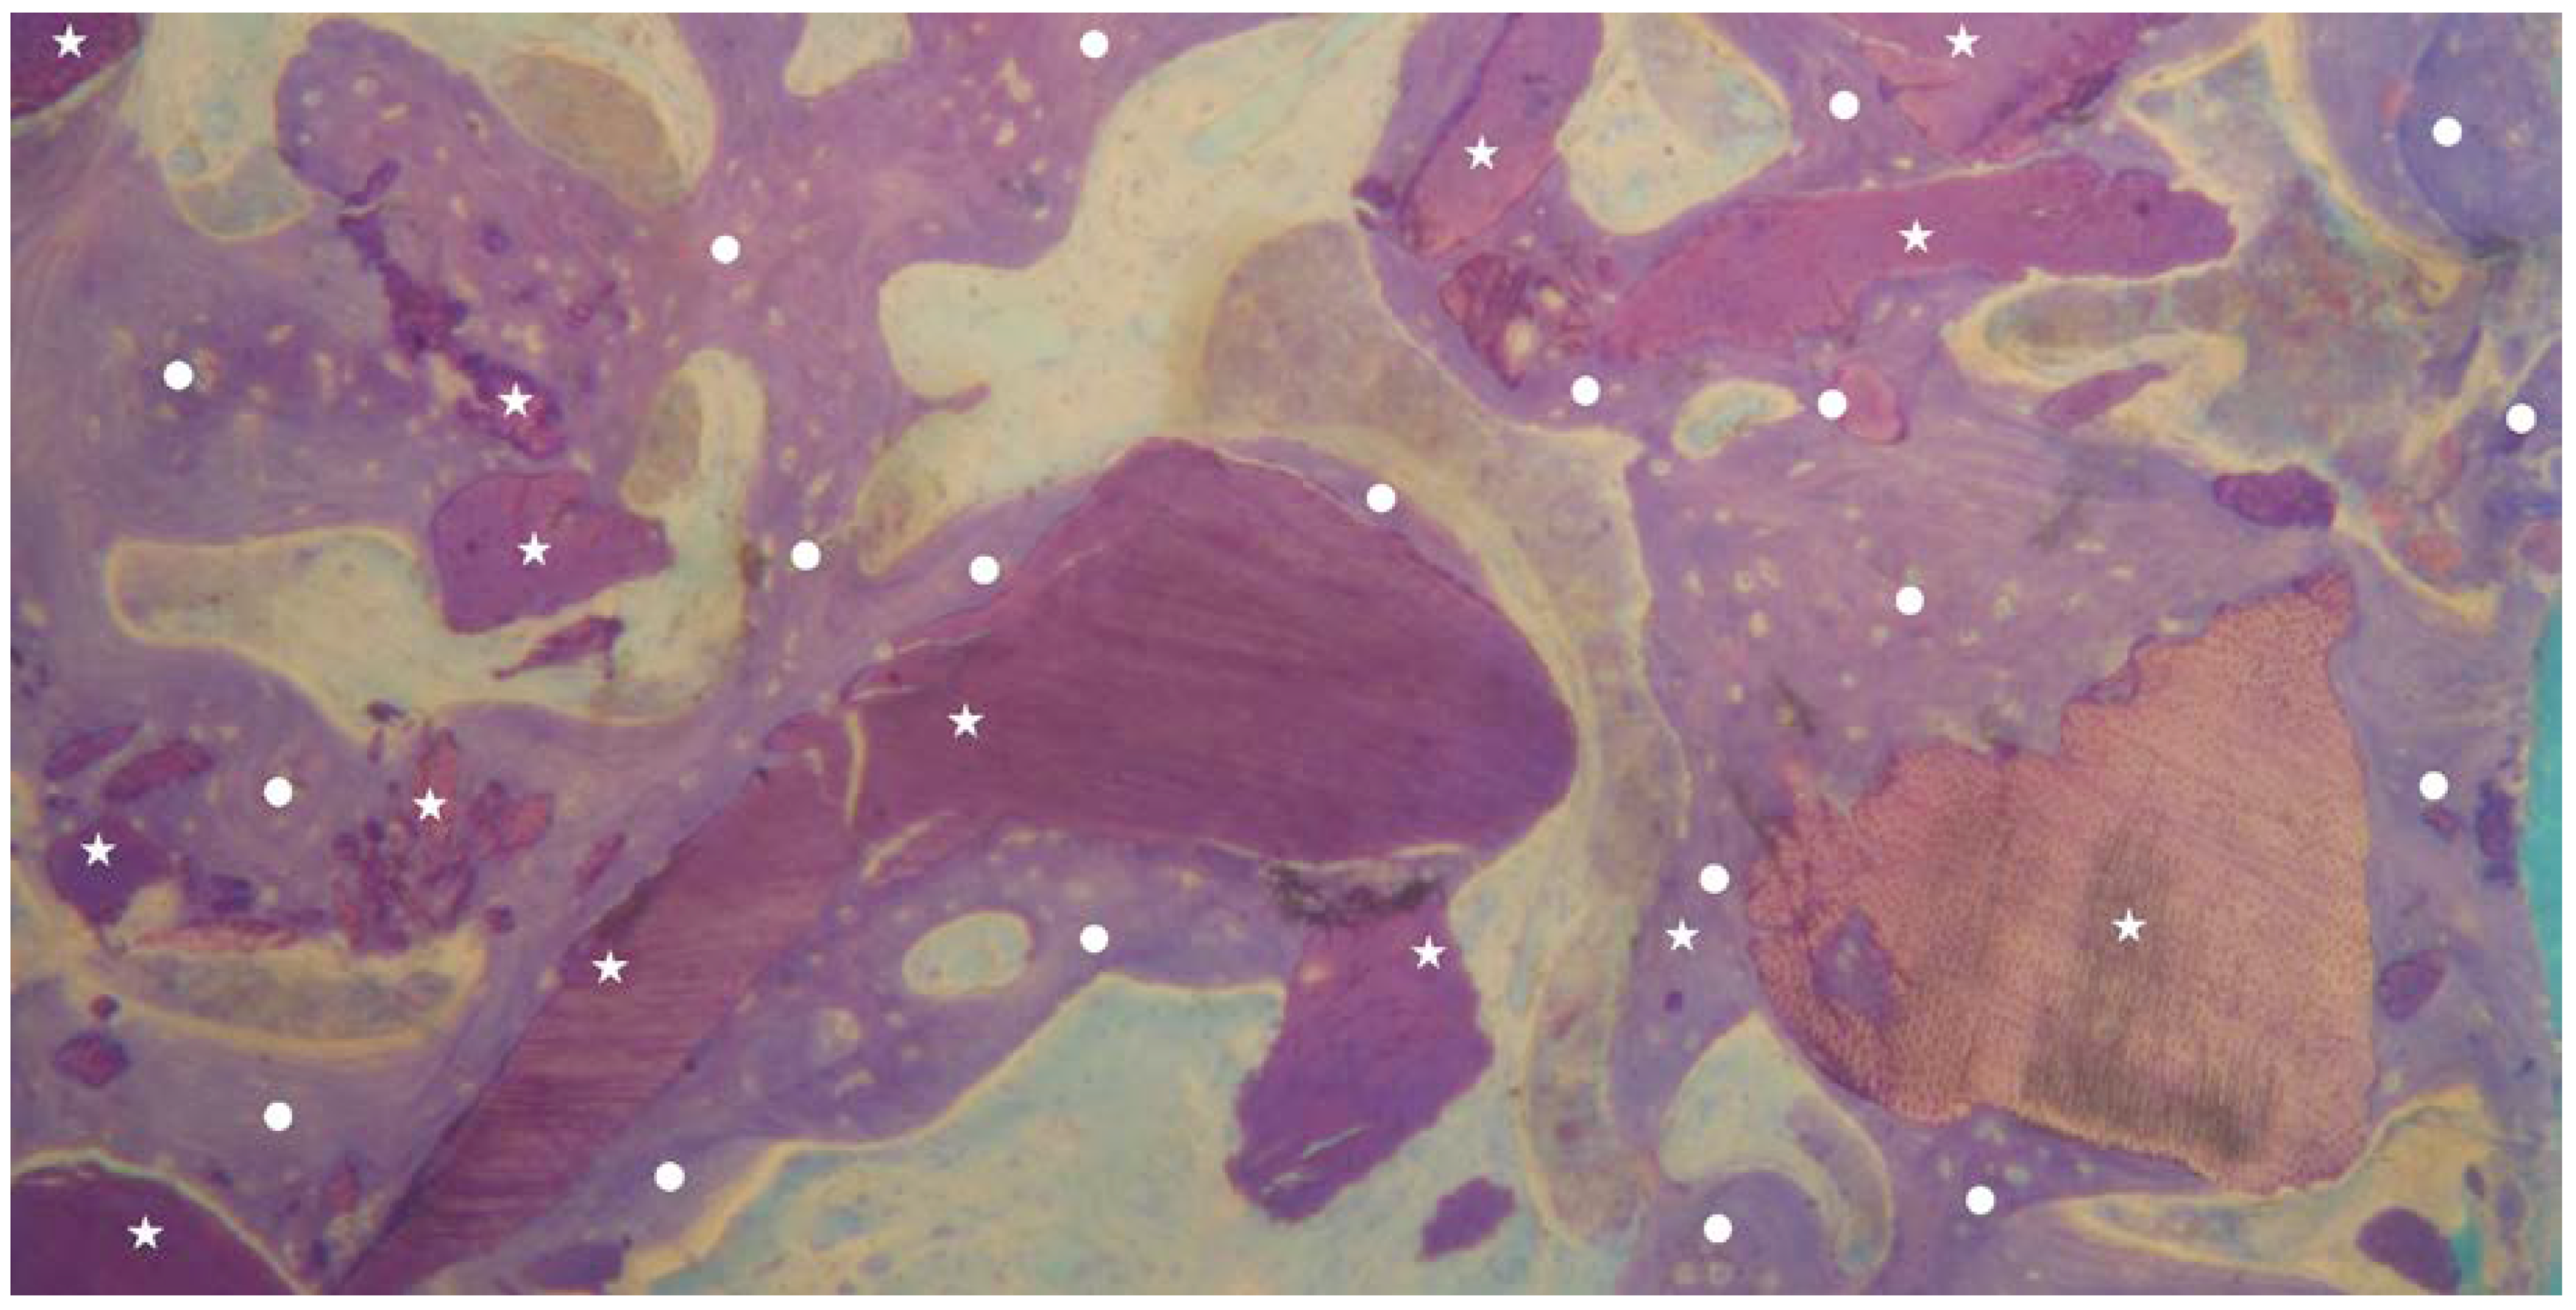

No inflammation signs were detected in all specimens (Figure 1 and Figure 2). No endodontic filling materials (gutta-percha, composite, cement, etc.) were detected in G2 samples (Figure 2). Histomorphometric analysis of the G1 biopsies showed a mean of 36.68% (±8.90%) for BV, 19.70% (±13.75%) for RG, and 20.78% (±13.29%) for VB (Figure 1 and Figure 3). In the G2 group, the histomorphometric analysis showed a mean of 39.16% (±11.51%) for BV, 17.39% (±7.09%) for RG, and 22.89% (±9.72%) for VB (Figure 2 and Figure 4). No statistical significance value (Table 5) was detected between the two groups.

Figure 2.

Overview of a biopsy at low magnification. Group 2: dentin matrix granules (indicated by white stars) and enamel granules (indicated by white squares) originating from endodontically treated tooth completely surrounded by newly formed bone (indicated by white circles) are visible. No inflammatory or other adverse reaction is visible around the particles (magnification 8×; toluidine blue).

Figure 4.

Group 2: newly formed bone trabeculae (indicated by white circles) and dentin matrix graft particles (indicated by white stars) are visible. It is possible to observe granules almost completely surrounded by new bone (indicated by white circles). No inflammatory or other adverse reaction is visible around the particles (magnification 25×; toluidine blue).